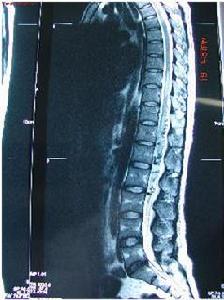

脊髓血管畸形1、Ⅰ型診斷在MRI上可以看到異常的血管但是在腰骶段脊髓,異常的T2加權信號往往是惟一的異常發現。脊髓硬膜動靜脈畸形的診斷在CTM往往更敏感和具特異性,與不用造影相比,在強化CT上於脊髓的背外側可以看到一個較大且呈捲曲狀的血管,造影時病人應取仰臥位進行,以檢查硬膜內的靜脈回流。硬膜動靜脈畸形中強化CT表現為完全阻塞者非常少見。在MRI上可以與髓內腫瘤相區別,MRI上可以顯示血液流空現象,這與脊髓周圍迂曲擴張的靜脈的表現相一致。脊髓硬膜動靜脈畸形的病人的MRI往往是正常的,如果病人的MRI結果正常而高度懷疑其患有脊髓硬膜動靜脈畸形,應進行脊髓造影。如果造影正常,通常沒有必要進行脊髓動脈造影

2、ⅡⅢ型診斷髓內動靜脈畸形病灶可通過T1加權像上的流空徵象加以識別。在T2加權像上常並有脊髓內出現異常信號,脊髓周圍的流空徵象提示脊髓病變周圍的部分。脊髓動脈造影在確定髓內病變上是必要的,但在區分Ⅱ型和Ⅲ型病變上並不總是有幫助。選擇性主動脈插管以及椎動脈、頸動脈和髂腰血管的插管造影在確定髓內病變供應的滋養動脈上是有必要的。背側和腹側的根血管經脊髓前動脈和脊髓後動脈分支供應動靜脈畸形。脊髓前動脈可能終止於髓內動靜脈畸形,或仍可能作為一段血管,可以確定脊髓動脈瘤和靜脈曲張。

4、海綿狀血管畸形診斷,海綿狀血管畸形的放射影像學圖像具有特徵性。在T1加權T2加權和質子密度成像上可以看到一個混合信號強度健康搜尋的中心。在T1加權上可以看到此中心被一個低密度的含鐵血黃素環包繞。這些病變通常沒有顯著增強。對具有波動性症狀的病人進行連續磁共振掃描,病變的體積可能有所變化。脊髓造影和血管造影很少有異常,通常不能做出海綿狀血管畸形的診斷。有時有必要行脊髓血管造影,對海綿狀血管畸形與其他類型的血管畸形區別。